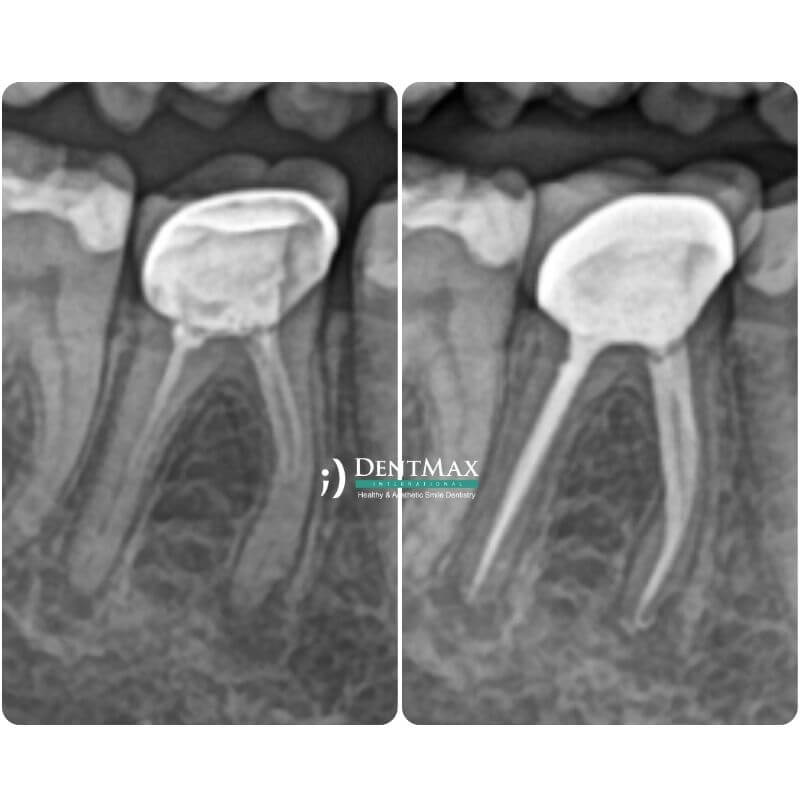

Повторное лечение канала